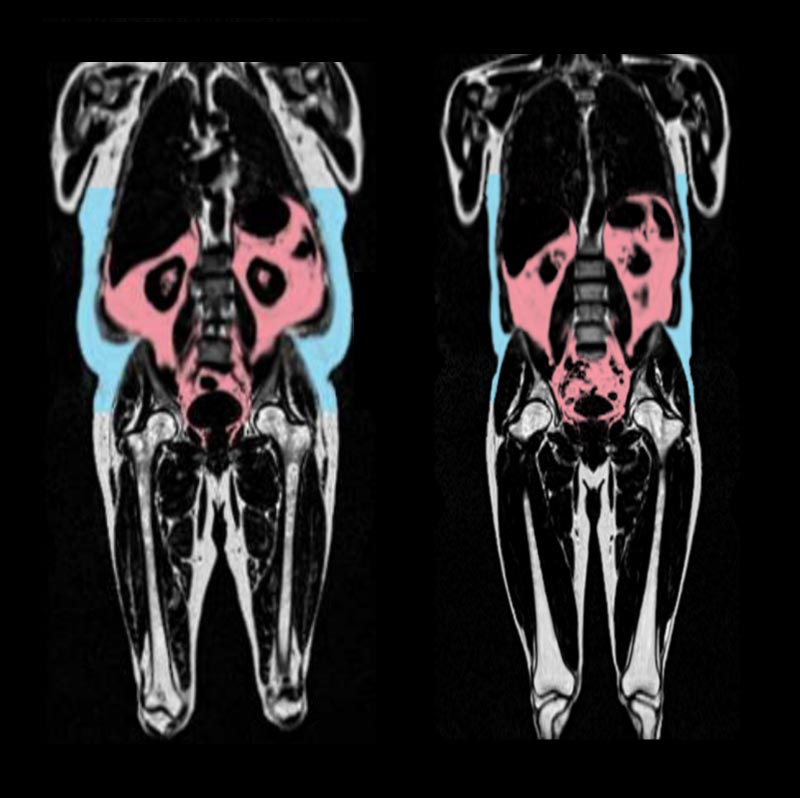

Вісцеральний жир — це «глибокий жир», що накопичується навколо внутрішніх органів у черевній порожнині, таких як печінка, шлунок і кишечник. Він невидимий неозброєним оком, тому його присутність важко виявити без спеціальних методів візуалізації. Як стверджує професор Деклан О’Реган, «поганий жир, прихований глибоко навколо органів, прискорює старіння серця». Саме цей тип жиру, за даними дослідників, найтісніше пов’язаний із жорсткістю та запаленням серцевих тканин, що є основними ознаками його старіння.

Науковці з Лондонської лабораторії медичних наук MRC використовували штучний інтелект (ШІ), щоб встановити так званий «вік серця» – умовний показник біологічного стану серця, що порівнюється з фактичним віком людини. У ході аналізу понад 21 тисячі зображень з UK Biobank було виявлено: чим більше вісцерального жиру, тим «старше» серце. Важливо, що індекс маси тіла (ІМТ) не показав високої точності в передбаченні віку серця. «ІМТ не є хорошим способом прогнозування віку серця», – наголосив О’Реган, підкреслюючи значення точного вимірювання розподілу жиру.

Виявлені гендерні особливості у розподілі жиру свідчать про глибші біологічні механізми. У чоловіків жир переважно накопичується в області живота, що формує так звану «яблукоподібну» фігуру, яка виявилась фактором ризику. Жінки ж частіше мають «грушоподібну» форму тіла – жир відкладається на стегнах і сідницях, і цей тип розподілу, за словами вчених, може захищати серце.

«Жир навколо стегон і сідниць у жінок може сповільнювати старіння серця», — зазначив О’Реган. Це пояснюється, зокрема, впливом гормону естрогену. У жінок у передменопаузі спостерігалося менше вікових змін серця, що дозволяє припустити: естроген може відігравати захисну роль у серцево-судинному старінні. Професор Брайан Вільямс також наголосив: «Оскільки характер розподілу жиру, який зазвичай спостерігається в організмі жінок, пов’язаний з естрогеном, цей гормон може стати ключовим у розробці майбутніх методів лікування старіння серця».